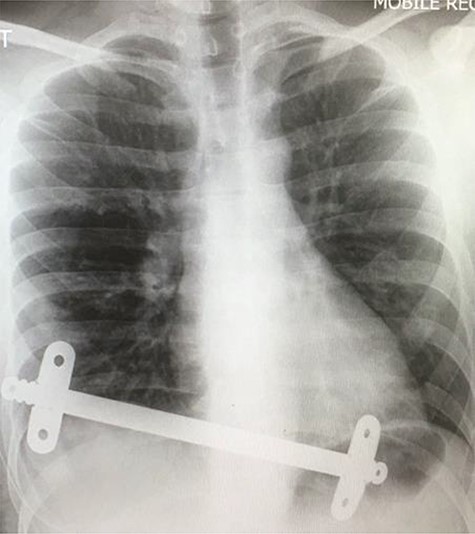

Superior lateral intraoperative view of the laparotomy used to access and remove the second migrated bar.

Our patient was followed up annually. After two and half years, he developed a right-sided wound infection, initially treated with antibiotics. It was decided to remove the bar for prevention of recurrent infection. The chest X-ray showed migration of the lower-placed bar (Fig. 2). The upper bar and associated stabilizers were removed through the bilateral small incisions without any complication; however, the lower bar was not palpable. Therefore, a left-side thoracotomy was performed; however, the bar was not found in the chest. The incision was extended to a midline laparotomy (Fig. 3). This revealed an erosion of the bar in to the stomach after passing over the left lobe of the liver (Fig. 4). The bar and stabilizers were completely removed, and the hole in the stomach was closed directly with sutures. The patient was discharged home without any further complication after successful recovery.